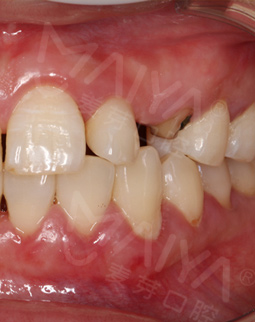

其实我更看重附加的价值,复诊了两次,没有额外收费,而且有专门人员提醒,医生态度一如既往的好,在麦芽种牙这个价格真的性价比很高了,毕竟材料、医生、种牙流程等等,我坚信种植牙是可以在我口内待一辈子的!而且就是第一次来的时候填个单子建个档案,后面我自己轻车熟路,直接去诊室,流程还是挺方便的,又节省时间。牙冠安装好了,很真牙没有什么两样,苦恼我多少年的问题终于在麦芽解决了!

拔牙种牙,就打麻药的时候有点感觉,其他的就是在牙椅上躺了一会就好了,手术时间很短,不到十分钟,种牙就结束了,真的种牙一点都不痛,种牙后的疼痛感也几乎为零,另外牙冠是定制的,需要等一段时间,用牙刷大小的东西扫了一下,就出现了模型,科技感很强!